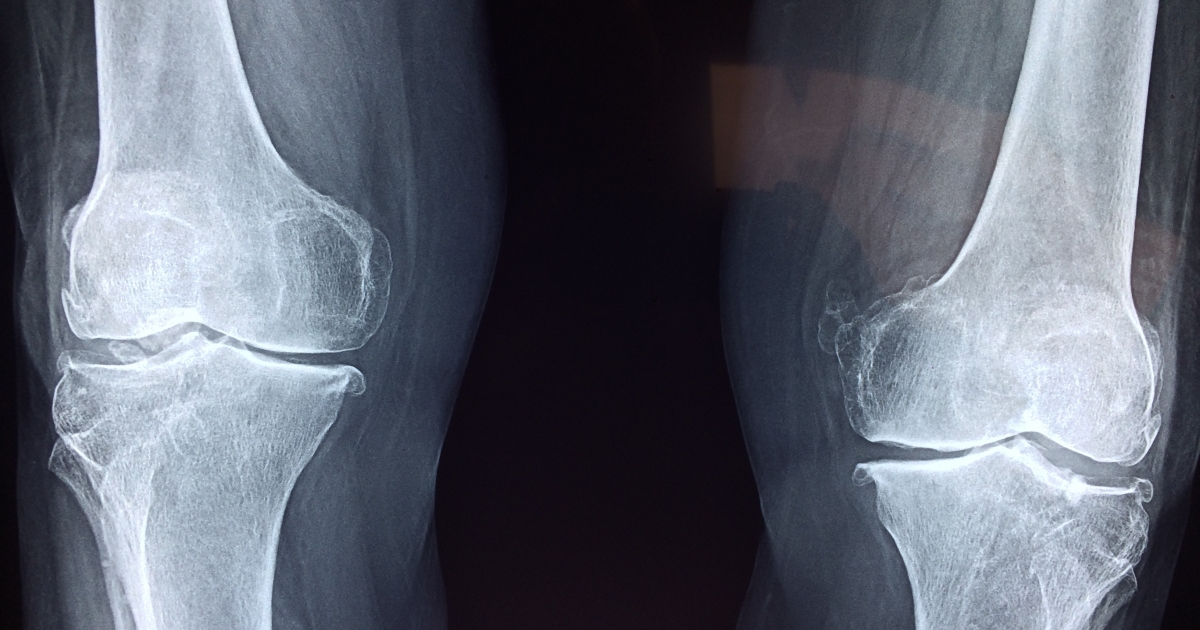

Photo credit to Dr. Manuel González Reyes